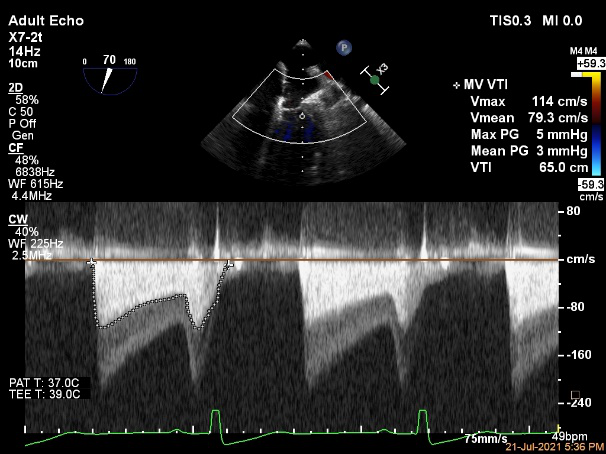

术前超声诊断:

长轴:左室下后壁节异,LAV:101ml,LVEDV:239ml

Bicom:MR(重度),返流束宽15.8mm,返流面积10.6cm²

PISA法定量EROA:0.69cm²,Rvol:168ml,RF:55%

肺静脉血流频谱呈收缩期反向

3D MV View

3D-color MV view:血流主要来源于2区近3区

Qlab软件勾画估测瓣口面积约:6.16cm²

二尖瓣口平均跨瓣压差:1mmHg

TEE Bicom返流量评估

TEE 4-Ch view返流量评估

夹子放置后二尖瓣口平均跨瓣压差:3mmHg

肺静脉血流频谱恢复正常